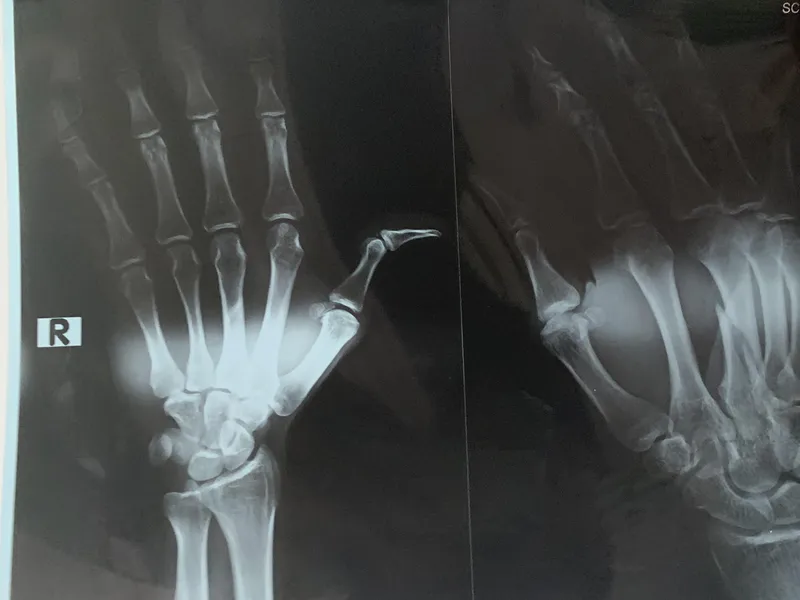

Sau quá trình thăm khám BS. CKII Phạm Văn Long chẩn đoán gãy cổ xương đùi (T) + tiền sử Đái tháo đường -> tiến hành phẫu thuật thay khớp háng (T) bán phần. Bệnh nhân H được đưa vào phẫu thuật tại Bệnh viện đa khoa Medic Bình Dương, BS. CKII Phạm Văn Long trực tiếp phẫu thuật. Case phẫu thuật thành công tốt đẹp, bệnh nhân được đưa xuống phòng lưu bệnh tại Bệnh viện đa khoa Medic Bình Dương để theo dõi.